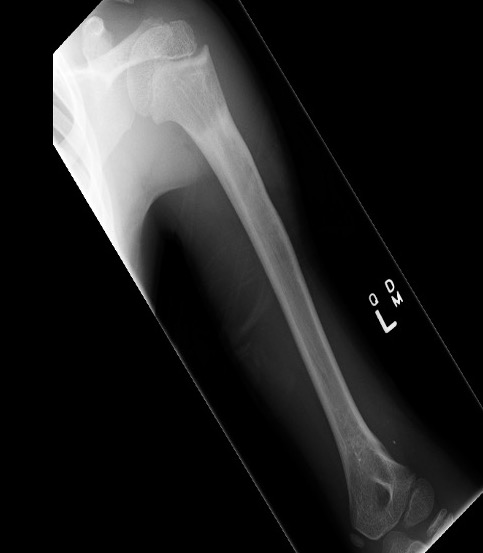

Case: 18 year old boy

Initial xray 18 month xray